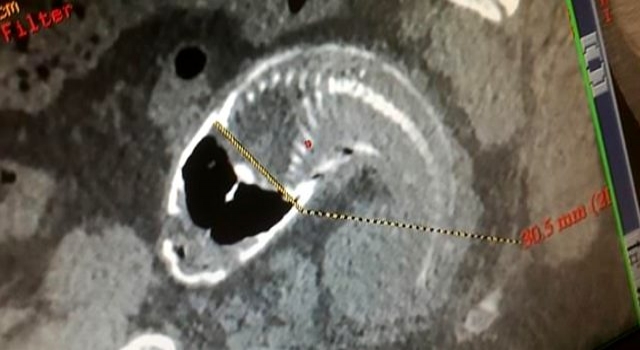

Çin'de 30 yaşındaki adam, yanlışlıkla 40 santimlik balığın üzerine oturunca tilapı tipi balık talihsiz adamın makatına kaçtı. Bir süre sonra şiddetli ağrıya dayanamayan adam, Guangdong şehrinde bulunan hastaneye gitti. Doktorlar, röntgenini çektikleri adamın makatında balık olduğunu görünce büyük şok yaşadı.

Talihsiz vatandaş, yaptığı açıklamada, yanlışlıkla balığın üzerine oturduğunu, çıkarmaya çalıştığını ama balık çok büyük olduğu için başarılı olamadığını söyledi. Balık sıkıştığı yerden ameliyat ile çıkarıldı.